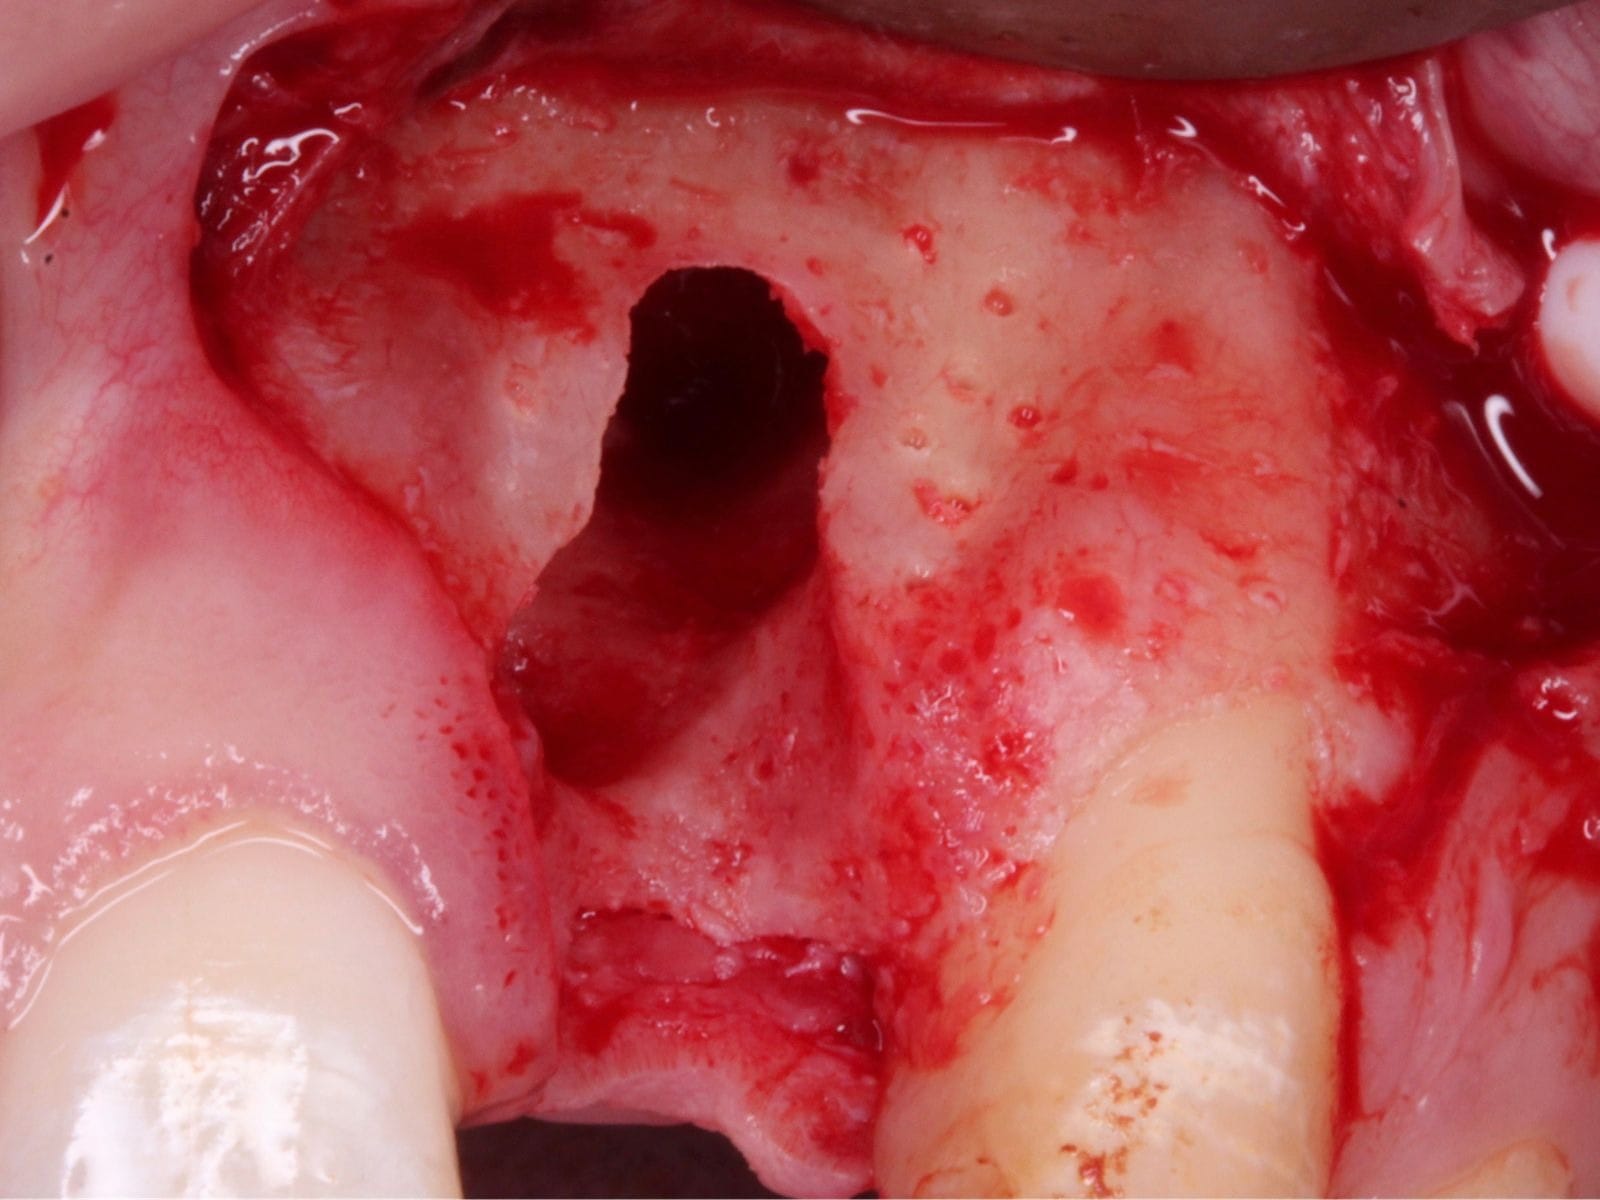

- Understand the principles of graft harvesting and management of the recipient and donor sites

- Practical application of site augmentation, including graft harvesting and managing recipient and donor sites - Use of Ossix Bone, Ossix Plus and Ossix Volumax

This course will teach you the fundamentals of soft and hard tissue grafting. Beginning with a brief revision of the periodontium, you will then learn how to identify patients who would benefit from such surgeries, as well as safe and effective ways to manage them. This includes suture technique and flap design, soft and hard tissue graft materials with specifications on the qualities and handling of each, and post-procedural management. Medico-legal advice and managing complications will also be discussed to help you gain a comprehensive view of this field.